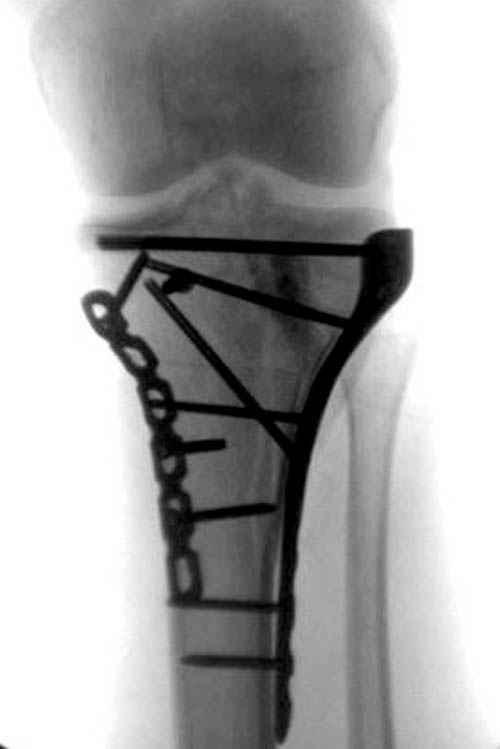

На боковом рентгене, явный задний смещенный компонент. КТ поможет увидеть "вершину" перелома, куда надо поставить антискользящую пластину из заднего или задне-медиальнего доступа. Для стабилизации боковой колонны традиционный боковой доступ через Girdle tubercle с длинной блокирующей пластиной. Одна задняя подпорка не удержит медиальную колонну, требуется длинная медиальная пластина.

Пластин для медиальной колонны не бывает, и поэтому подойдет любая тонкая пластина. Сегодня отходим от установки для тибиал плато толстых пластин, больше, чем 3.5 мм. Задача удержать, а нагрузка разрешается только после сращения в 3 мес., и поэтому нет смысла устанавливать толстые пластины

Перелом сложный, и для окончательного успеха потребуется арсенал фиксаторов и наличие опыта разных доступов. К успеху приведет только тщательное планирование. Возможно, фиксировать не удастся все за раз. Если во время операции возникнет опасность развития отека в ране, “damage control” операцию надо отложить, лучше поэтапно, чем осложнение.